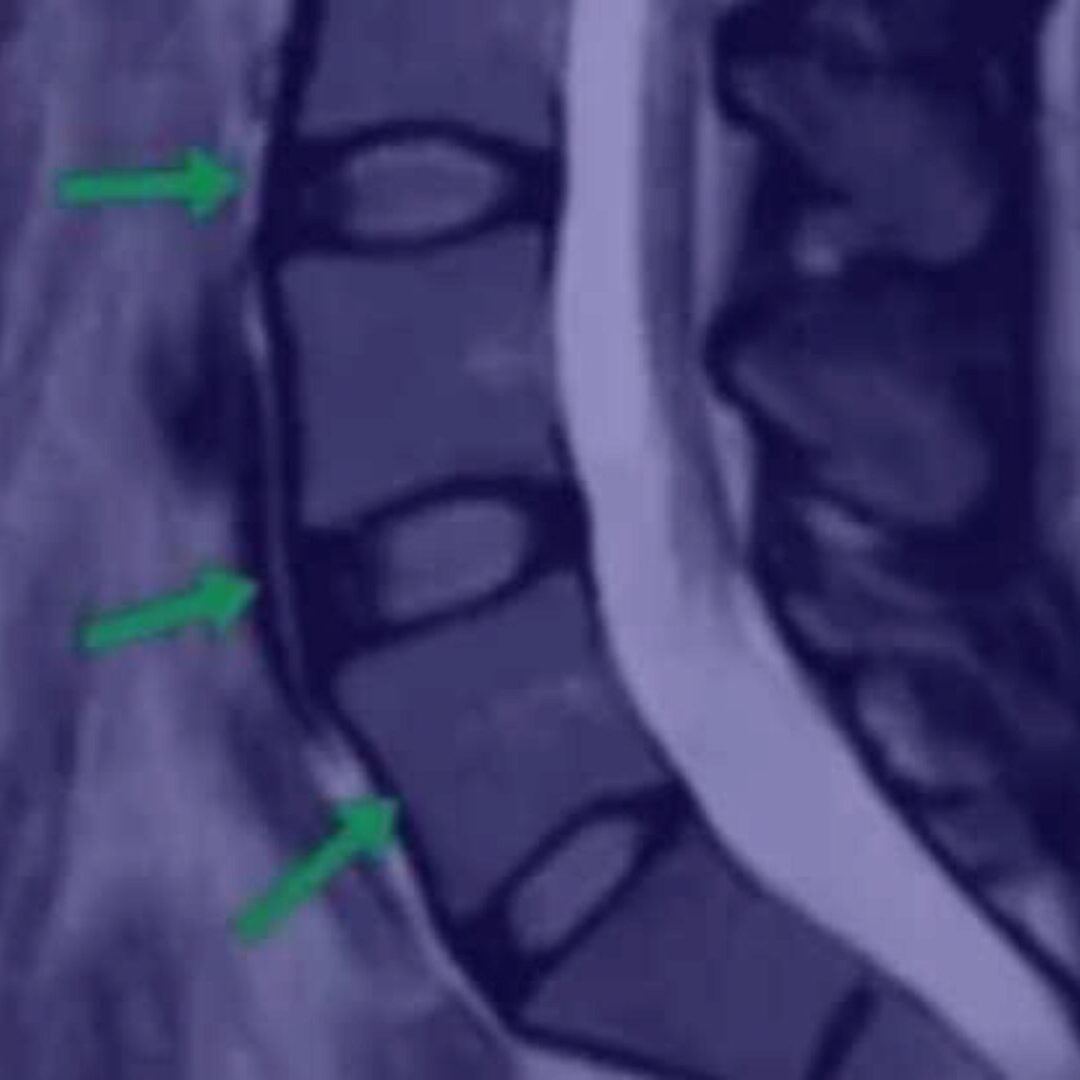

- Что оценивать на МРТ

- Как выглядит идеальный позвоночник

- Как выглядит плохой позвоночник

- Как выглядит позвоночник спортсмена

- Надрыв кольца на МРТ, поясничный прострел

- Протрузия на МРТ

- Грыжа осложненная стенозом канала

- Секвестрированная грыжа

- Артроз на МРТ

- Позвоночник пациента, занимающегося тяжелым физическим трудом

- Остеопороз, перелом позвонка

- Кисты на суставах

- Гипертрофия фасетки

- Листезы

- Гемангиомы

- Гипертрофия желтой связки

- Грыжа Шморля